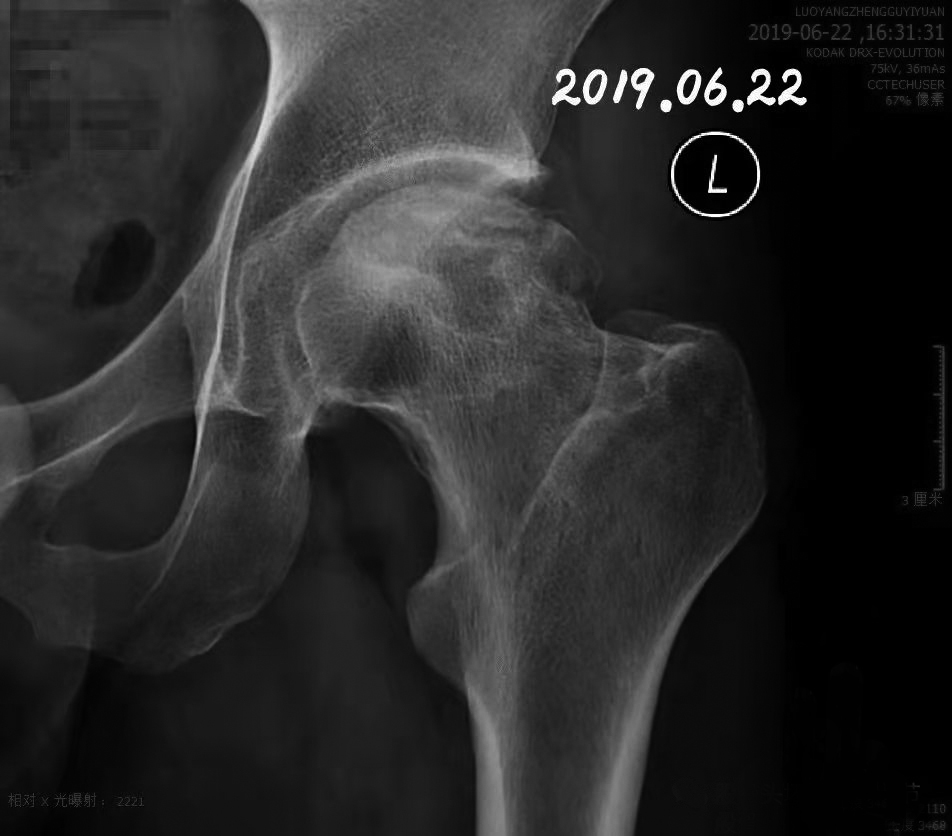

股骨头坏死的原因复杂多样,坏死的部位也比较多,有的是全头坏死,有的是前方坏死,有的在外侧,有的在后外侧,有的在内侧,有的呈点状,有的由点连片……其中,波及外侧柱的股骨头坏死,一般患者无论手术与否,塌陷率均较高。对这类患者的治疗,对医生是一个很大的挑战。 我今天介绍一个病例。一位35岁的男性患者,整个外侧柱均受波及,股骨头塌陷,是换还是保? 从患者的影像图(图1)可以看出:股骨头已经塌陷,关节面毛糙,坏死面积很大…… 划一下重点,看图2,箭头1、2、3、4表示关节面节裂的部位,箭头5、6、7、8表示坏死的范围,可以看到外侧柱压缩碎裂。 如果有足够的勇气,这个时候赌一把还是可以的:进行植骨重建。 但是,医生给不了患者治愈的承诺,患者也不愿意尝试做手术,这就比较尴尬了。 果不其然。尽管不断进行保守治疗(中药、西药+冲击波),患者的股骨头还是继续塌陷。但是,让人感到有一点欣慰的是,股骨头坏死的范围似乎在缩小。 患者的蛙位片显示情况不容乐观,可以看到骨头周围有骨赘形成。 股骨头坏死的治疗往往不会一帆风顺,治疗过程很考验医生的耐心和患者的勇气。继续治疗,患者可能面临金钱和时间的双重损失。 又过了4个月,患者进行复查。 正位片提示,股骨头的骨质重建似乎又有所改善,关节面变得更加连续。 蛙位片给人的整体感觉是股骨头内不稳定,骨生成与骨吸收处于一个矛盾的不平衡状态——这继续考验着医生和患者的耐心与毅力。 患者自我感觉疼痛减轻了,可影像检查结果提示好像在加重! 疗效评价的标准有两个方面:一是影像,二是患者的疼痛和功能情况。 不好取舍,也无法做出预测。 在犹豫和不安中,患者断断续续治疗了一年,来到医院进行复查。 正位片显示骨密度减低区明显缩小,外侧柱没有继续塌陷。 侧位片显示之前的关节面节裂消失,关节间隙没有明显变窄,骨坏死区也修复得比较完美。这是一个让人兴奋的结果。 患者获得了一个无痛、功能接近正常的关节。太不容易啦! 很多人会质疑,偶然的因素导致了这样的成功,不值得推广和炫耀。 回过头来看,这个病例存在一定成功基础。根据影像学检查结果可以得知,患者的骨密度并不太差,提示存在自身修复的能力,而不是一旦坏了就破罐子一摔到底的类型;中药、西药联合冲击波,对坏死区的修复做到了精准、高效治疗;根据病情适当拄拐、进行分期功能锻炼,有利于股骨头关节面的模造(通过持续的力学刺激,达到对股骨头的塑形、改造,以达到更适合头臼同心圆的要求)和修复。 通过持续、适当的力学刺激,对修复中的股骨头不断塑形、改造,以达到适合头臼同心圆的要求,有利于恢复关节功能。 只是这样的病例对医生和患者来说都是双重考验:既考验医生对病情的分析、预后的判断,又考验患者能否坚持、能否承受得起失败。 怎么说呢?治病需要医患双方为了一个共同的目标一起努力。而医生,肯定是希望患者尽快痊愈的人。 (作者供职于河南省洛阳正骨医院)